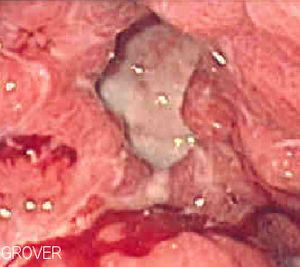

المظهر كما يرى بالعين المجردة

ينحصر وجود القرحة المعدية غالبا على الانحناء الأصغر فيها ويُرى كعيب " ثقب" دائري أو بيضاوي الشكل يتراوح قطره من 2 إلى 4 سنتيمترات في جدار المعدة متميز بقاعدة مصقولة وملساء وحواف قائمة الانحدار، لكن هذه الحواف لا تكون مرتفعة أو غير متناسقة كما تكون حواف الثقوب في سرطانات المعدة المتقرحة. يظهر على الغشاء المخاطي المحيط أيضا طيات شعاعية بسبب الندوب الموجودة في الجدار.

مصطلح طبي يعني الجرح المفتوح، أي تآكل جزء من الأنسجة وتسمى حسب موقعها. فإذا وقعت في الغشاء المخاطي للجهاز الهضمي سميت بالقرحة الهضمية. وتكون عادة دائرية الشكل وبيضاء اللون يرافقها بعض الاحمرار (احتقان) على حوافها.